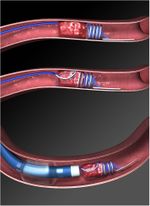

انحلال الخثرة

استئصال الخثرة آلياً

رأب الوعاء والدعامات